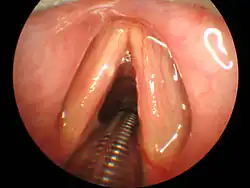

Vue laryngoscopique de l'orifice glottique.

Vue laryngoscopique de l'orifice glottique.